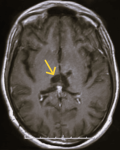

Diagnostic assessment: magnetic resonance imaging of the brain demonstrated an infiltrative thalamo-peduncular lesion with hyperintensity on T2/FLAIR sequences and faint enhancement on post-contrast T1, raising concern for an infiltrative high-grade glioma and creating diagnostic uncertainty (Figure 1, Figure 2). A stereotactic biopsy was subsequently performed. Initial histological evaluation suggested a high-grade glioma; however, immunohistochemical staining revealed strong positivity for CD117, PLAP, and OCT4, findings consistent with a pure germinoma (Figure 3, Figure 4). Staging with thoraco-abdominopelvic CT identified nonspecific pulmonary micronodules (Figure 5), while serum tumor markers remained within normal limits (Table 1). As shown above, the patient's LDH level is elevated compared to the reference range, while both β-HCG and α-FP are within normal limits. These values are important for the diagnostic evaluation and ongoing management of intracranial germ cell tumors.

Figure 1: contrast-enhanced brain magnetic resonance image showing a thalamo-peduncular lesion: axial T1-weighted post-contrast magnetic resonance image demonstrating a thalamo-peduncular mass with heterogeneous patchy enhancement and multiple small cystic components (red arrow)

Figure 2: axial T2-weighted brain magnetic resonance image showing a thalamo-peduncular mass: axial T2-weighted magnetic resonance image demonstrating a hyperintense lesion in the thalamo-peduncular region with surrounding edema and compression of the third ventricle